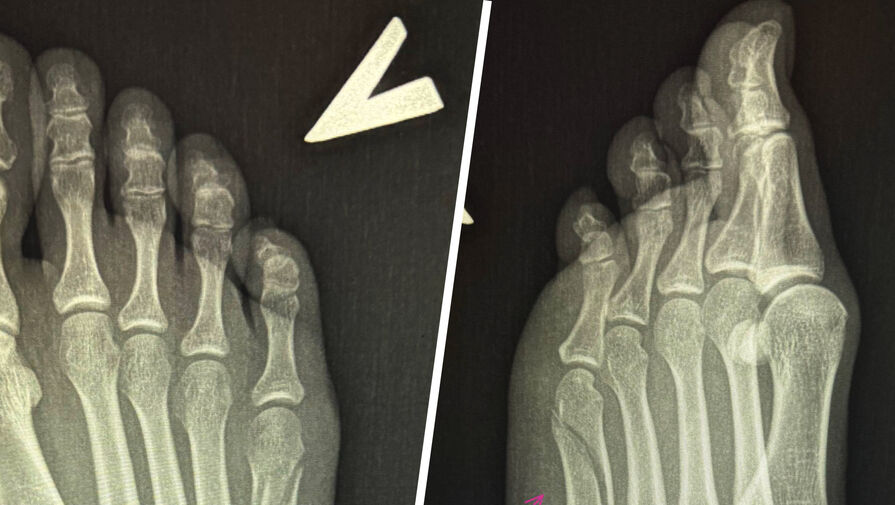

Вавилова опубликовала сообщение в ночь на 28 сентября 2025 года, приложив к нему рентгеновские снимки, на которых видна трещина в кости, ведущей к мизинцу. Она отметила, что из-за травмы не может заниматься привычными делами и вынуждена оставаться дома для отдыха.